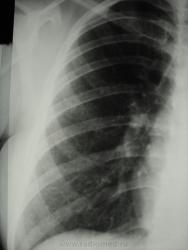

По рентгенограммам, создается впечатление превалирования "изменений", преимущественно, в средних и нижних отделах легочных полей.

Изменения диффузны. По rg более выраженны в нижних отделах, за счет марсива тканей. Ждем анализ мокроты и промывных вод.